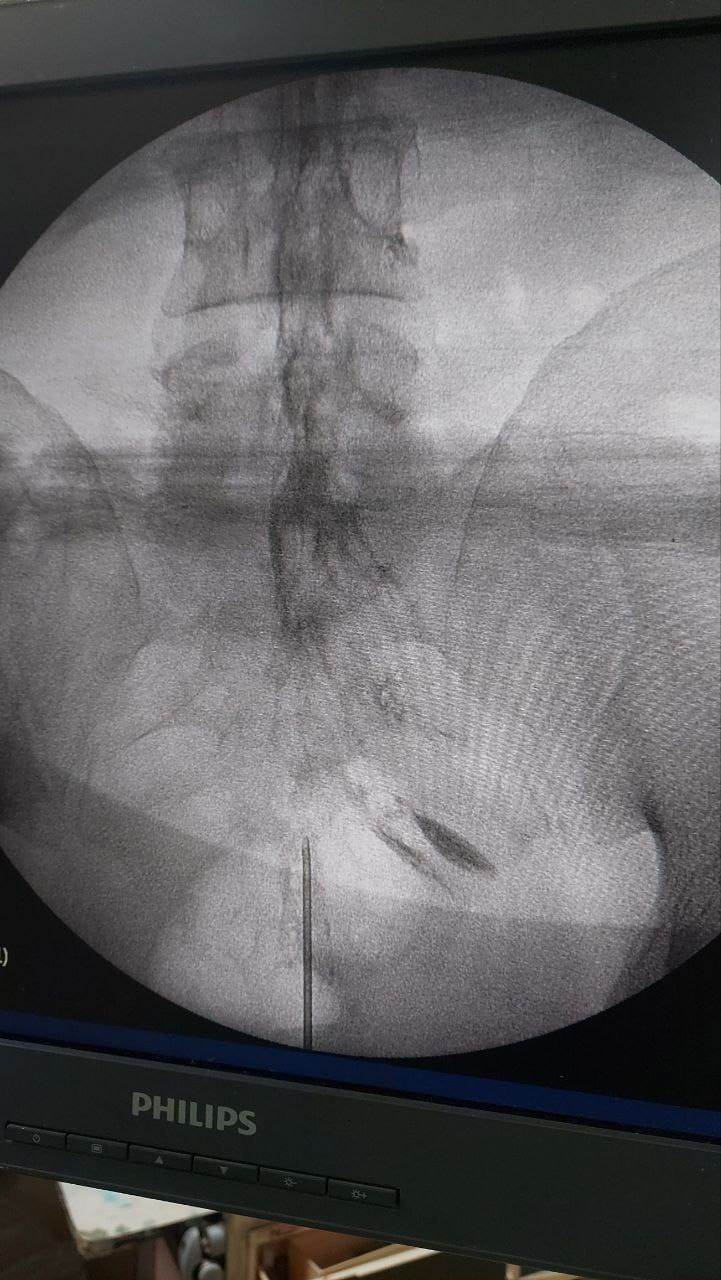

Procedures